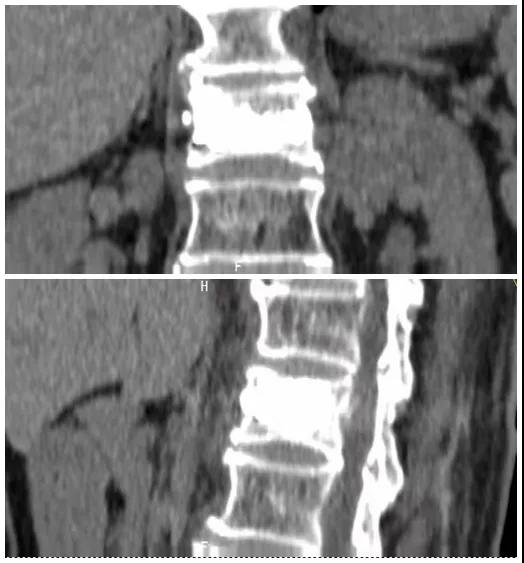

術(shù)前磁共振檢查提示腰1椎體新鮮壓縮性骨折

術(shù)后復(fù)查CT可見骨水泥彌散充分

經(jīng)術(shù)前分析詳細(xì)評估,由骨科副主任張宏宇及科室團(tuán)隊(duì)順利為患者進(jìn)行了經(jīng)皮穿刺椎體成形術(shù),術(shù)后患者疼痛明顯減輕。同時(shí),科室團(tuán)隊(duì)還為她制定了科學(xué)的抗骨質(zhì)疏松治療,目前患者已康復(fù)出院。